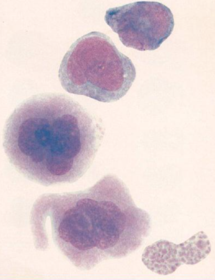

Es la maduración de las células linfocíticas, la célula madre hematopoyética da origen a la célula madre linfoide de donde maduran los linfocitos (Rodak, 2004). Linfoblasto Célula de 10 a 18 micras, es redonda, con relación núcleo:citoplasma aumentada, núcleo redondo, céntrico y basófilo con nucleicos presentes, la basofilia es relativa a la cantidad de ARN presente. El citoplasma es casi invisible por el gran tamaño del núcleo (Rodak, 2004).

Fuente: Rodak, E. (2004). Hematología: Fundamentos y Aplicaciones. (2da ed.). Madrid, España: Editorial Médica Prolinfocito La relación núcleo:citoplasma ha disminuido, el núcleo es redondo basófilo, no se observan los nucleolos, el citoplasma es escaso y acidófilo. Ya presentan los receptores que van a diferenciar a cada tipo de linfocito, pero no son funcionales (Rodak, 2004).

Pueden salir de la médula ósea, siendo prolinfocitos para madurar en el bazo dando origen a los linfocitos B o quedarse en la médula ósea dando origen a los linfocitos T. Esto dependera de qué tipo de células se necesiten en el organismo. Fuente: Rodak, E. (2004). Hematología: Fundamentos y Aplicaciones. (2da ed.). Madrid, España: Editorial Médica

Linfocito Mide aproxidamadamente 9 micras, tiene un núcleo oval central basófilo y escaso citoplasma que presenta escasos gránulos azurófilos. Es la célula ya madura y funcional (Rodak, 2004). La diferencia entre ambos tipos de linfocitos está en los receptores y su función, no se logran diferenciar en el microscopio al microscopio. Los linfocitos T tienen receptores TCR y los linfocitos B tienen BCR que reconocen a un antígeno específico (Rodak, 2004).

Tanto los linfocitos T, como B pierden su morfología al ser altamente activos, llamándoles linfocitos "atípicos" o células de Downey. Estos por su forma llegan a confundirse con monocitos, la diferencia está en la mayor condensación de los cromosomas de los linfocitos (Rodak, 2004). Los linfocitos T al estar activos son difíciles de diferenciar, pues tienen a perder y volver a adquirir los receptores, con dos objetivos: 1. ser más específicos y 2. proliferarse cuando no posean los receptores en sus membranas (Rodak, 2004).